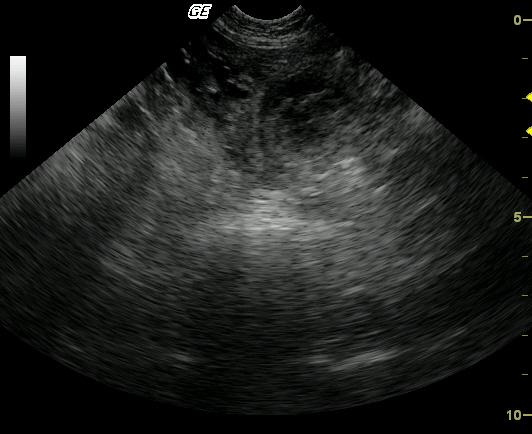

An 8-year-old MN DLH cat was presented with a 3-day history of lethargy, vomiting, and diarrhea. A palpable abdominal mass was present on physical examination. The initial blood chemistry profile revealed severely elevated ALT and severely elevated AST with moderate azotemia and a mildly elevated creatinine concentration. Urinalysis revealed a specific gravity of 1.059 and hematuria. Moderate non-regenerative anemia also was evident.